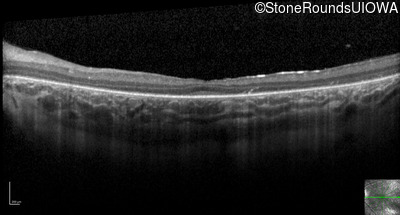

Optical Coherence Tomography - Right - 20/80 -1

Exemplar / OCT Stack